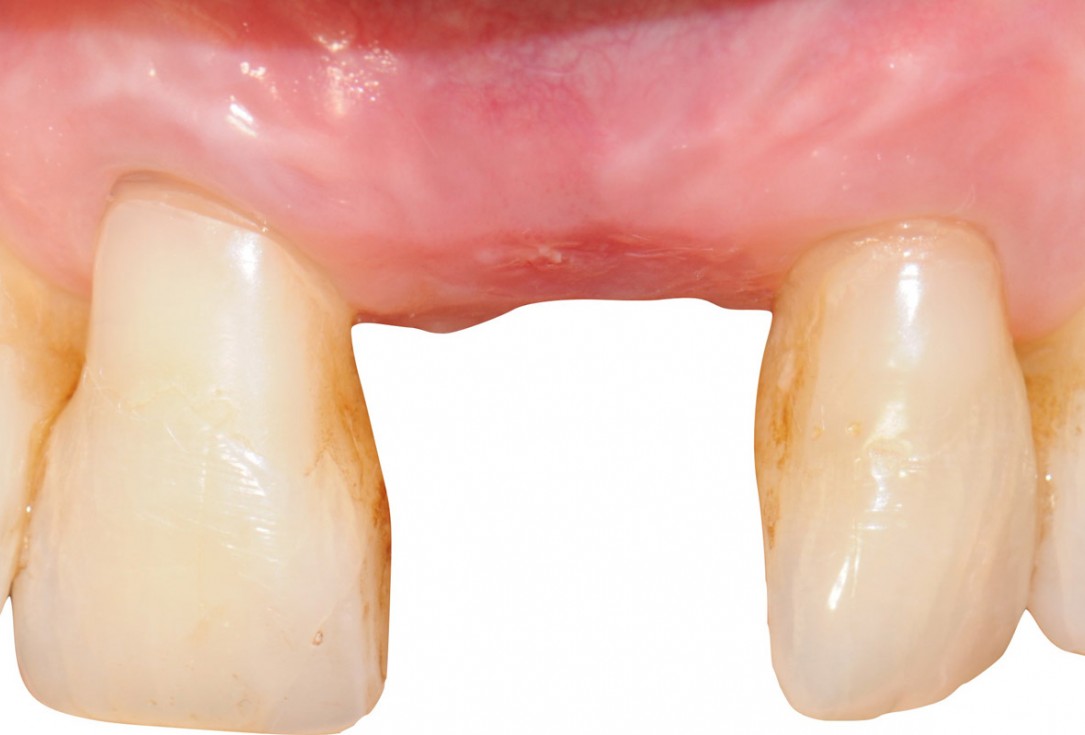

13/18 - 8 weeks after surgeryTooth extraction and socket sealing with mucoderm® - Dr. A. Rossi

14/18 - 8 weeks after surgery, occlusal viewTooth extraction and socket sealing with mucoderm® - Dr. A. Rossi